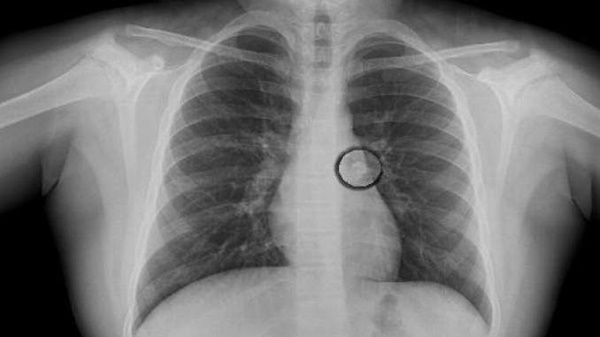

Các bác sĩ đã thực hiện chụp X-quang và phát hiện chiếc răng nằm ở phế quản chính bên trái đường thở dẫn đến phổi trái của cô. Các bác sĩ phẫu thuật đã phải tiến hành phẫu thuật nội soi phế quản bằng sợi quang để lấy chiếc răng ra. Sau thời gian điều trị, bệnh nhân đã được ra viện.